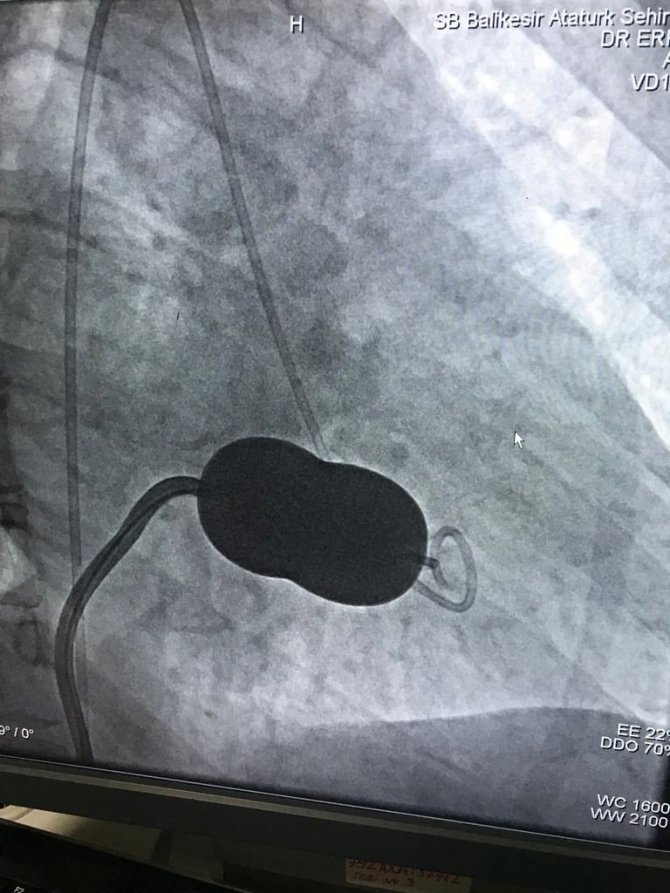

Başarılı operasyonlara imza atan hastanenin kardiyoloji doktorları uyguladıkları yöntemle Balıkesir'de yine bir ilki gerçekleştirdi. Kalp romatizması sebebiyle ileri derecede daralmış mitral kapak hastalığı olan E.A. isimli hasta, kardiyoloji bölümünden Doç. Dr. Erkan Aşhan ve ekibi tarafından Balıkesir Atatürk Şehir Hastanesi'nde ilk defa uygulanan mitral balon yöntemi ile başarılı şekilde tedavi edildi.

Doç. Dr. Erkan Ayhan yapılan tedaviyle ilgili şunları dile getirdi: "Hastamız ciddi kapak darlığı nedeni ilaç tedavisine yanıt alamadığımız felç riski taşıyan bir hastamız idi. Bu hastamızda genel anestezi kullanmadan mitral kapak darlığını balon yöntemi ile açtık. Tedavisine vesile olmak, şifa olmaktan büyük mutluluk duymaktayız. Kardiyoloji ile ilgili anjiografi hizmetlerimizi Sayın Başhekimimiz ve İl Sağlık Müdürlüğü sayesinde merkezimizde tüm olanakları ile yürütmekteyiz. Bu yöntem hastanemizde ilk defa uygulandı. Balıkesir ilinde böyle bir merkezimizin olması Balıkesir halkı adına büyük bir kazanç olmakla birlikte ne kadar hayati önemi olduğunu halkımızın bilgilerine sunarız."